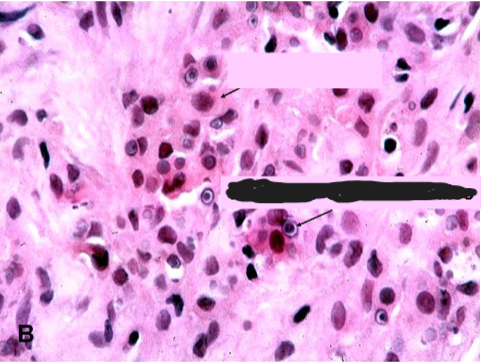

Malakoplakia

usually in context of chronic bacterial infection or immunosuppressed transplant patients

Path → sheets of macrophages with abundant granular cytoplasm (Phagolysosomes with bacterial fragments) & mineralized inclusions (Michaelis-Gutmann bodies)

Soft, yellowish plaques

concentrically layered Michaelis-Guttman bodies

Macrophages with abundant eosinophilic granular cytoplasm

Michaelis-Gutmann body

Michaelis-Gutmann bodies containing Iron & Calcium